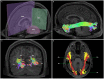

The human inferior longitudinal fasciculus (ILF) is a ventral, temporo-occipital association tract. Though described in early neuroanatomical works, its existence was later questioned. Application of in vivo tractography to the neuroanatomical study of the ILF has generally confirmed its existence, however, consensus is lacking regarding its subdivision, laterality and connectivity. Further, there is a paucity of detailed neuroanatomic data pertaining to the exact anatomy of the ILF. Generalized Q-Sampling imaging (GQI) is a non-tensor tractographic modality permitting high resolution imaging of white-matter structures. As it is a non-tensor modality, it permits visualization of crossing fibers and accurate delineation of close-proximity fiber-systems. We applied deterministic GQI tractography to data from 30 healthy subjects and a large-volume, averaged diffusion atlas, to delineate ILF anatomy. Post-mortem white matter dissection was also carried out in three cadaveric specimens for further validation. The ILF was found in all 60 hemispheres. At its occipital extremity, ILF fascicles demonstrated a bifurcated, ventral-dorsal morphological termination pattern, which we used to further subdivide the bundle for detailed analysis. These divisions were consistent across the subject set and within the atlas. We applied quantitative techniques to study connectivity strength of the ILF at its anterior and posterior extremities. Overall, both morphological divisions, and the un-separated ILF, demonstrated strong leftward-lateralized connectivity patterns. Leftward-lateralization was also found for ILF volumes across the subject set. Due to connective and volumetric leftward-dominance and ventral location, we postulate the ILFs role in the semantic system. Further, our results are in agreement with functional and lesion-based postulations pertaining to the ILFs role in facial recognition.